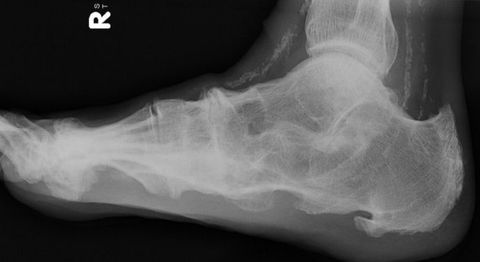

What disease is this? | Osteoarthritis |

What disease is this? | Gout |

What disease is this? | Tophaceous gout. |

What disease is this? | Monckeberg’s arteriosclerosis |

What disease is this? | Atrophic neuroarthropathy |

What disease is this? | Charcot Neuroarthropathy |